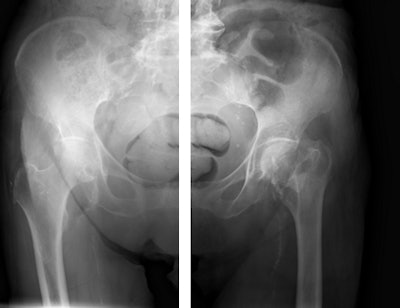

Tomosynthesis image of an ankle taken with Shimadzu's RADspeed Pro digital radiography system.The emphasis of Philips' researchers has been on developing technologies for improving diagnostic quality while eliminating inefficiencies when using mobile digital radiography systems at the patient's bedside. The new SkyFlow scatter correction algorithm reduces the effect of scattered radiation for nongrid bedside chest exams, allowing the operator to obtain DR images with grid-like contrast, but avoiding the time and effort involved in attaching and detaching a grid.

Pelvic radiographs taken with and without SkyFlow scatter suppression algorithm. Image courtesy of Philips.